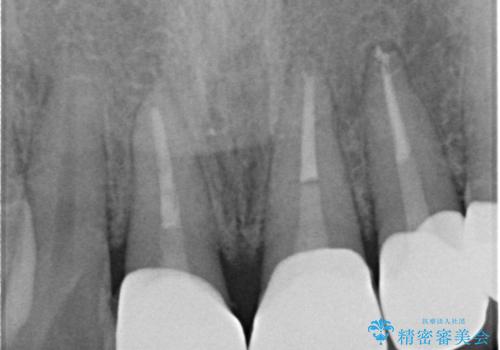

歯の神経の状態を見たところ、前歯3本とも神経が死んでしまっていました。

根の治療を行い、ぐらつきに関しては様子を見て連結をするとのお話をさせていただきました。

- 81.4万円 内訳:ジルコニアクラウン(スタンダード)11万円×4本 /精密根管治療 前歯、イニシャル 6万円×3本 /ファイバーコア 2万円×3本 /仮歯 1万円×3本/フラットタイプナイトガード 3万円費用は治療当時の料金となります

今後事故の影響でほかの歯の神経が死んでしまったり、状態が変化する可能性があるため経過観察が大事になってきます。